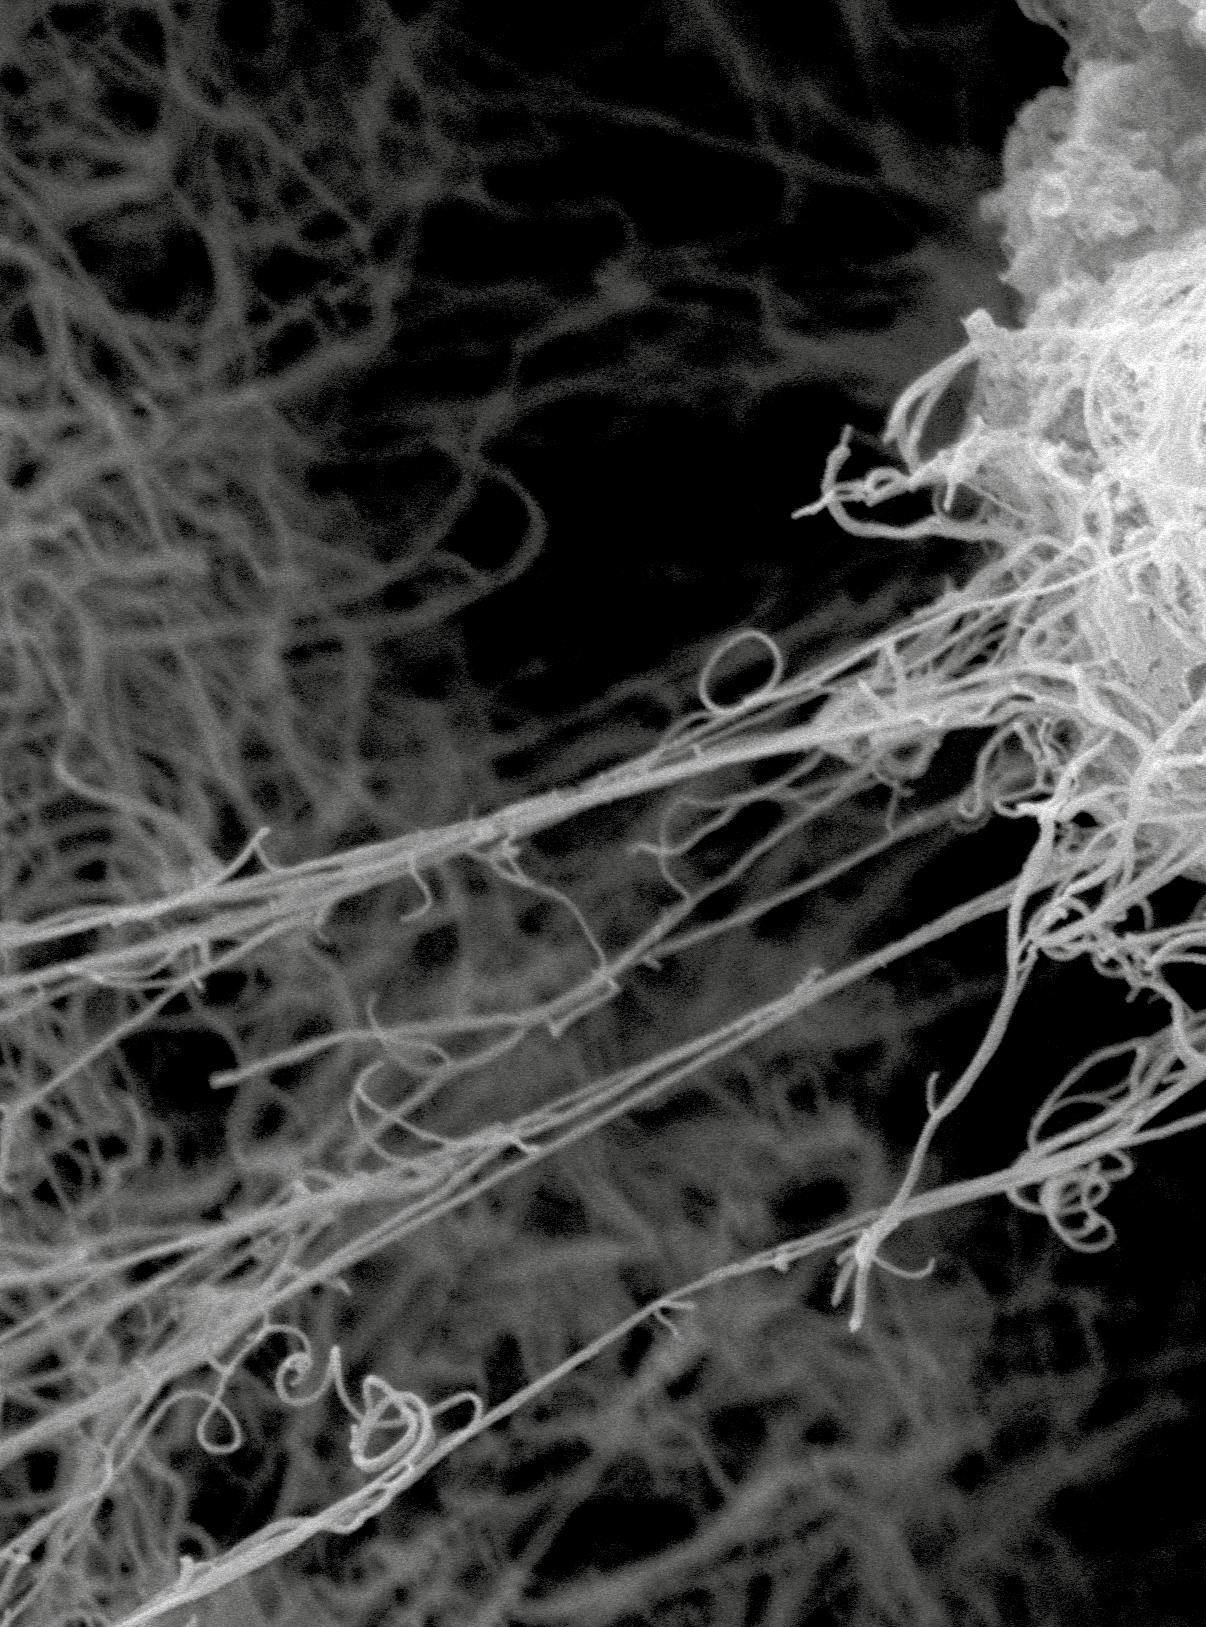

Geles de fibrina con fibroblastos en su interior visualizados por microscopía electrónica de barrido. Foto: cortesía del proyecto.

Uno de los enfoques para tratar y prevenir las infecciones en las heridas en la piel está representado por los modelos conocidos como equivalentes cutáneos o modelos tridimensionales de piel. Se trata de tejidos construidos en laboratorio, en este caso con células y fibrina, los cuales pueden ser modificados por ingeniería genética para que adquieran la capacidad de producir en grandes cantidades unas pequeñas proteínas conocidas como péptidos antimicrobianos, que contribuyen a la defensa natural de la piel. El Grupo Ingeniería de Tejidos y Terapias Celulares de la Universidad de Antioquia, en un esfuerzo colaborativo con el Departamento de Ingeniería Biomédica de la Universidad de Groningen, desarrolló un equivalente de piel que produce uno de estos péptidos conocido como péptido antimicrobiano LL-37, compuesto por 37 aminoáci-

dos (unidades estructurales de las proteínas). Este pequeño péptido ha demostrado ser capaz de destruir diferentes tipos de bacterias y de interaccionar y perforar las membranas bacterianas, lo que lo hace diferente de los antibióticos tradicionales, ya que estos últimos matan a las bacterias al inhibir procesos celulares específicos como la síntesis de proteínas bacterianas y la replicación del material genético. Por lo tanto, la inducción de resistencia bacteriana a los antibióticos a través del LL-37 es poco probable, pues los cambios en la estructura de la membrana celular de las bacterias ocurren raramente. La síntesis y secreción de LL-37 se observa principalmente en las células epiteliales, como los queratinocitos que se mencionaron antes, pero la producción de este péptido no se ha identificado en los fibroblastos. Por lo tanto, estimular la producción del LL-37 en las células que son utilizadas en la construcción de los equivalentes cutáneos hace que estos equivalentes puedan usarse, a su vez, para prevenir infecciones en heridas cutáneas.

Luego de confirmar que las células tenían en su interior la información genética que les adicionamos y verificar si eran capaces de producir el péptido LL-37, estas se utilizaron para la construcción de los equivalentes cutáneos modificados. Primero, se elaboró una especie de gelatina (gel de fibrina) con fibroblastos dentro de ella, y posteriormente se depositaron los queratinocitos sobre el gel. Después de 21 días en cultivo en el laboratorio observamos que las capas superficiales correspondientes a lo que podría ser la epidermis se habían desarrollado, por lo que evaluamos cómo era su forma y si producían el péptido LL-37. Encontramos que los equivalentes modificados tenían características del tejido muy similares a las de la piel normal. Además, localizamos la presencia del LL-37 tanto en las capas dérmicas como epidérmicas, lo que se evidencia con una coloración especial y particular en las células que lo producen. Este hallazgo demostró que los fibroblastos también estaban produciendo nuestro péptido de interés, es decir, el LL-37.